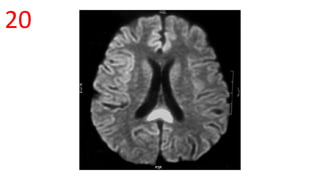

Huntington disease

Box-Car ventricle sign

• caudate nuclei are partially atrophied with

enlargement of the frontal horns

• The intercaudate distance to inner table

ratio (CC:IT) is increased (N = 0.9-1.2)

• frontal horn width to intercaudate

ratio (FH:CC) is decreased (N = 2.2-2.6 ).